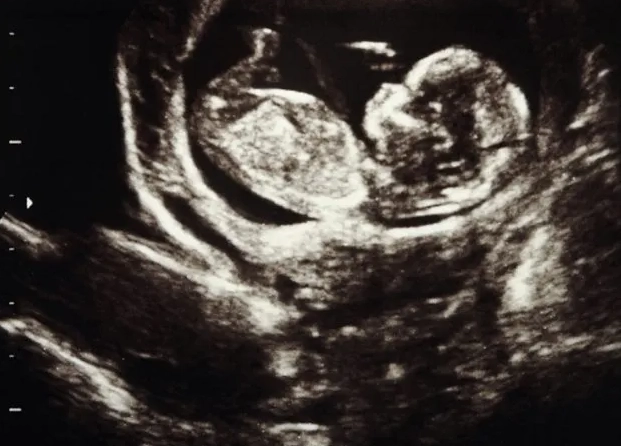

2. Ultrasound Scans

Ultrasounds track physical development. Key markers include:

- Crown-rump length (early pregnancy)

- Head circumference and abdominal circumference

- Femur length

- Presence of all major organs

- Amniotic fluid levels